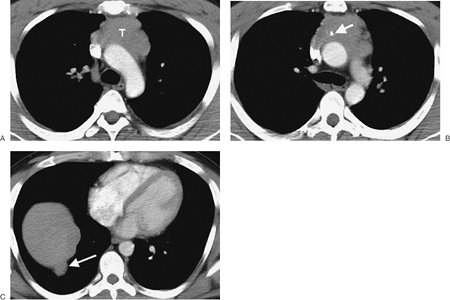

FIGURE 6-12. Malignant thymoma. A: CT scan shows a lobulated mass (T) of homogeneous soft tissue attenuation in the anterior mediastinum. B: CT scan at a level inferior to (A) shows course calcification (arrow) within the mass. C: A "drop" metastasis (arrow) is seen along the right hemidiaphragm.